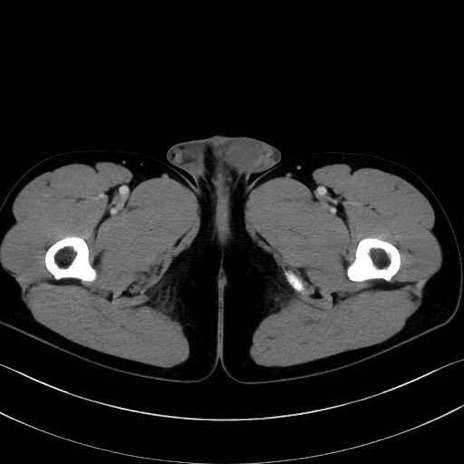

大腿方形筋 (Quadratus femoris)